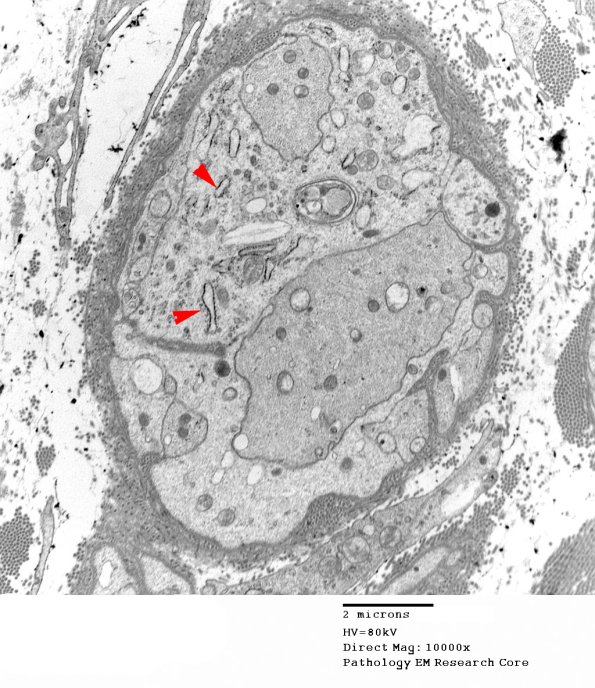

A different patient shows several regenerating axons within Schwann cell cytoplasm. In this case resolving the pale processes as Schwannian is facilitated by the presence of ribosomes (arrow). (electron micrograph)